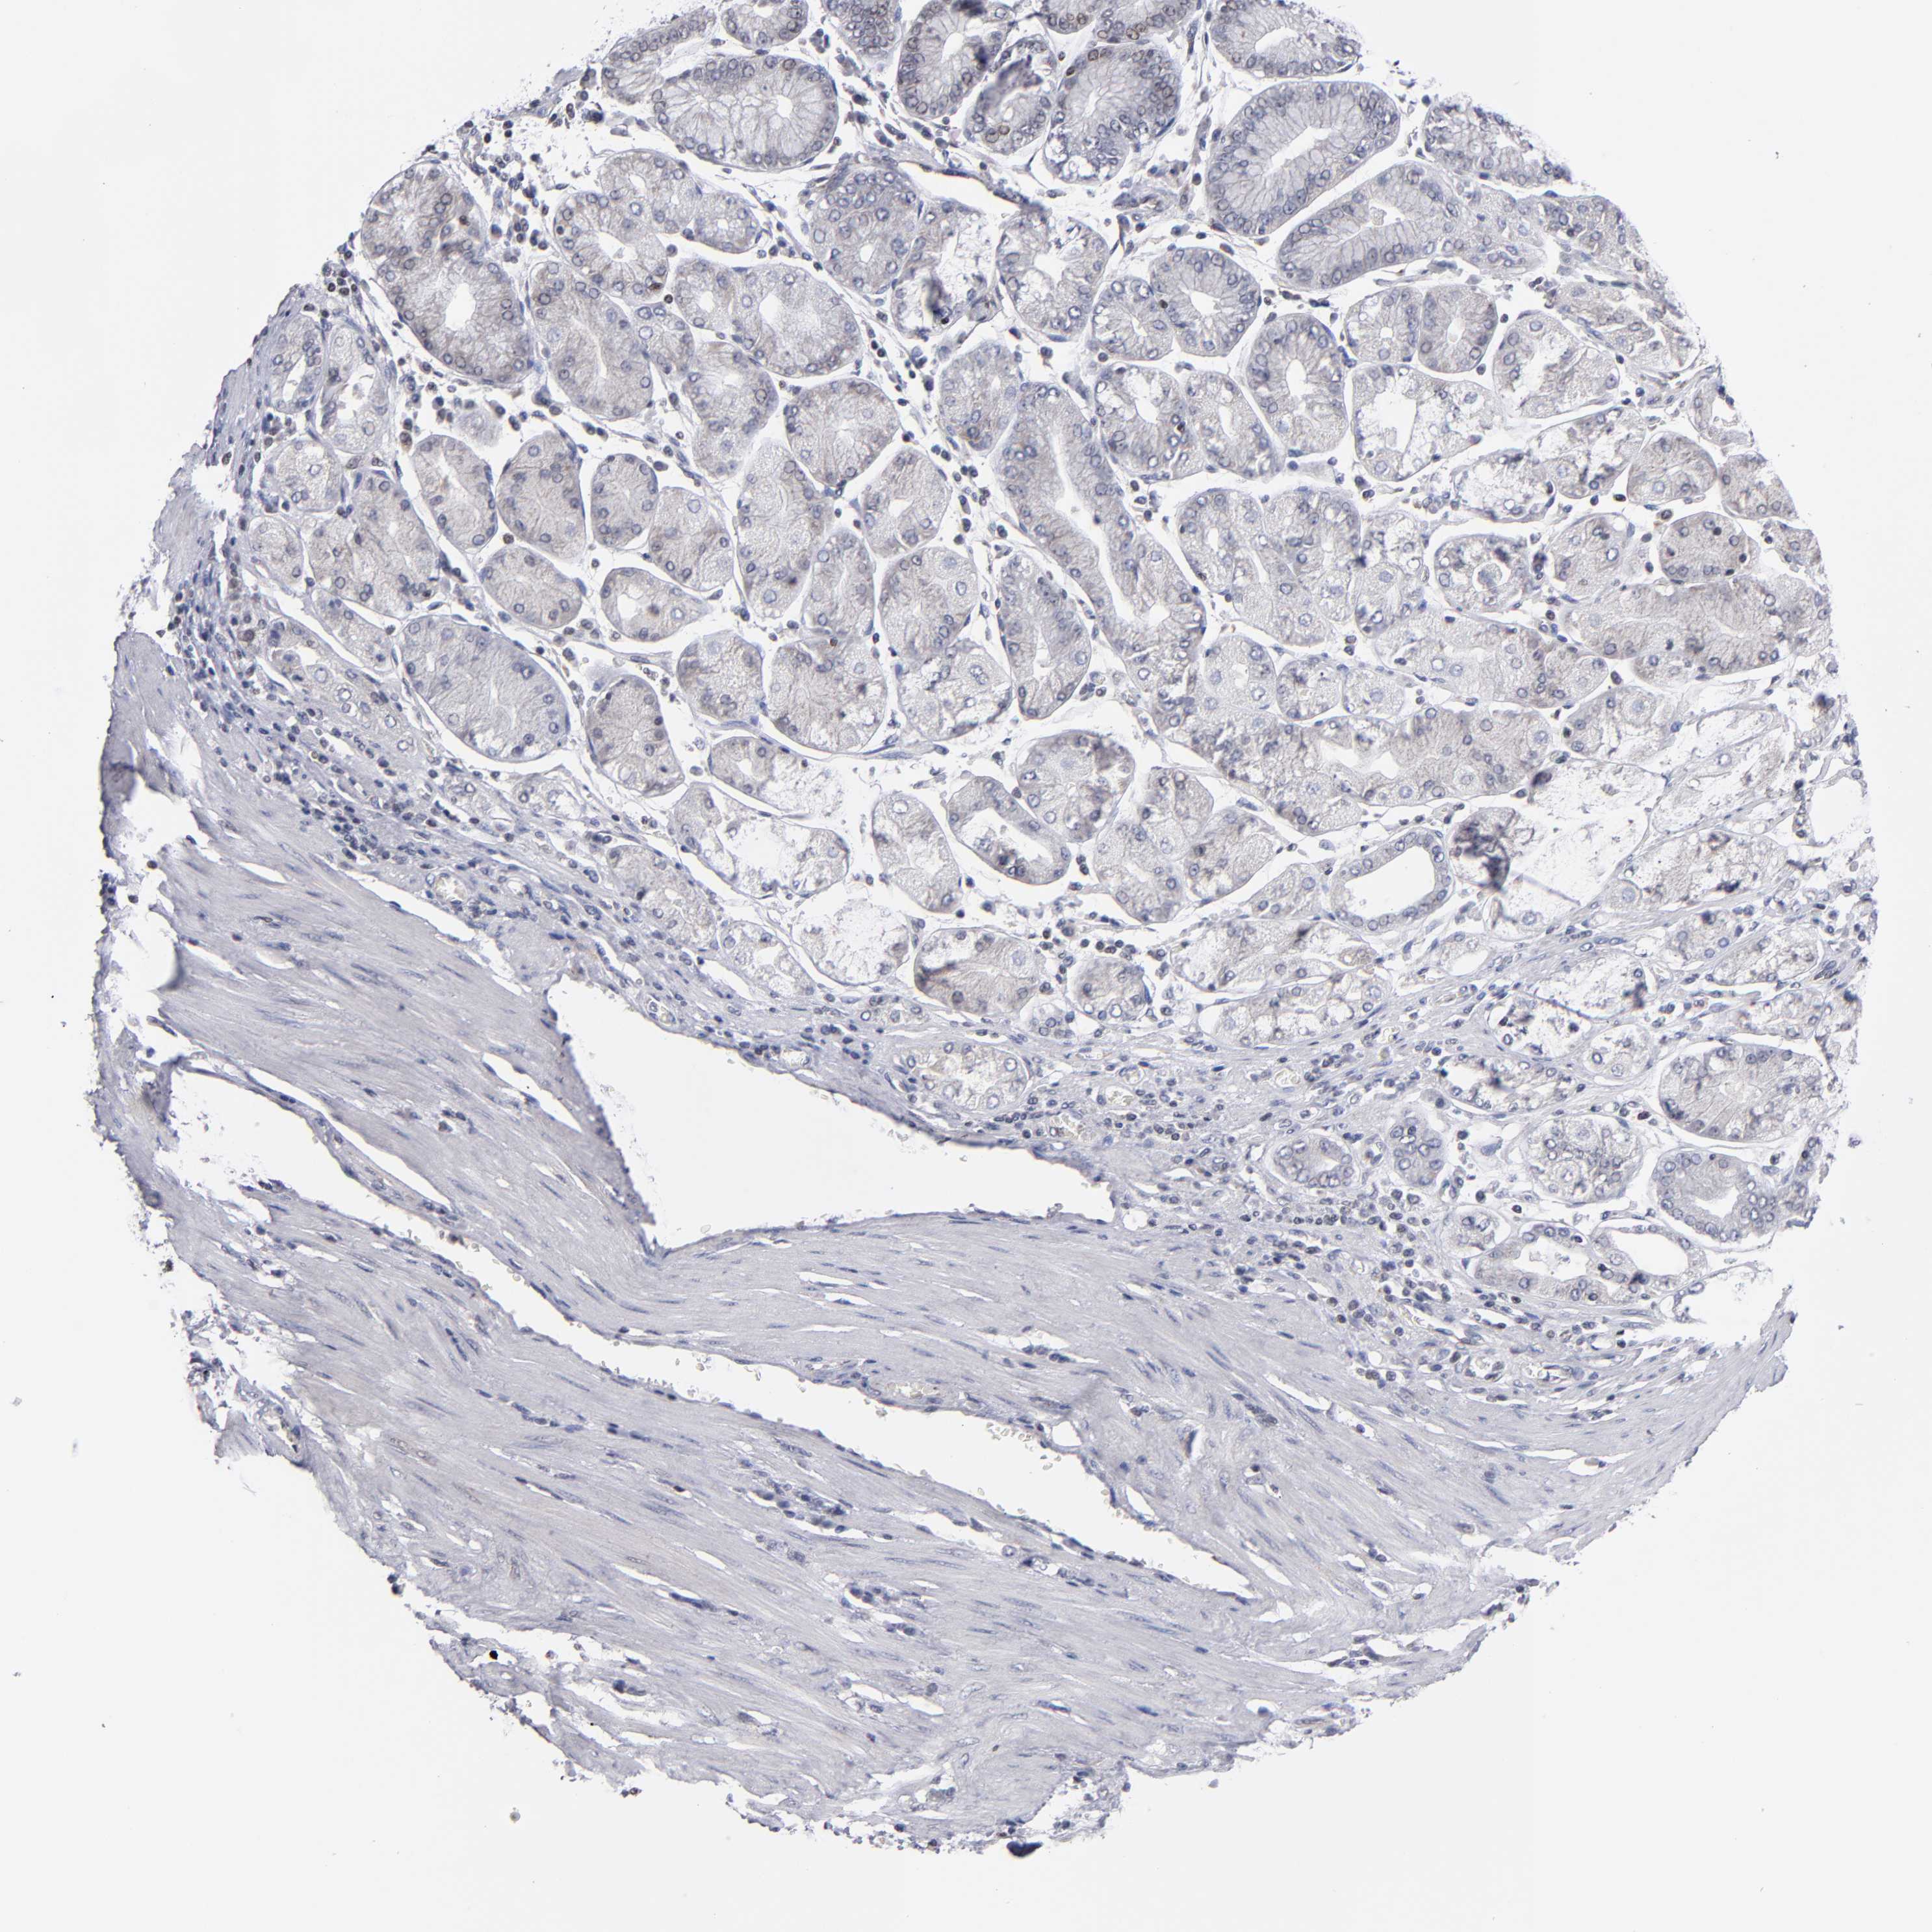

STOMACH CANCER - Protein expressioni

A mouse-over function shows sample information and annotation data. Click on an image to view it in a full screen mode. Samples can be filtered based on level of antibody staining by selecting one or several of the following categories: high, medium, low and not detected. The assay and annotation is described here.

Note that samples used for immunohistochemistry by the Human Protein Atlas do not correspond to samples in the TCGA dataset.

Antibody stainingi

Antibody staining in the annotated cell types in the current human tissue is reported as not detected, low, medium, or high, based on conventional immunohistochemistry profiling in selected tissues. This score is based on the combination of the staining intensity and fraction of stained cells.

Each image is clickable and will lead to virtual microscopy that enables deeper exploration of all samples and also displays staining intensity scores, fraction scores and subcellular localization as well as patient and tissue information for each sample.

Antibody HPA001874

Staining

High

Medium

Low

Not detected

Intensity

Strong

Moderate

Weak

Negative

Quantity

>75%

75%-25%

<25%

None

Location

Nuclear

Cytoplasmic/membranous

Cytoplasmic/membranous,nuclear

Adenocarcinoma, NOS

Adenocarcinoma, High grade